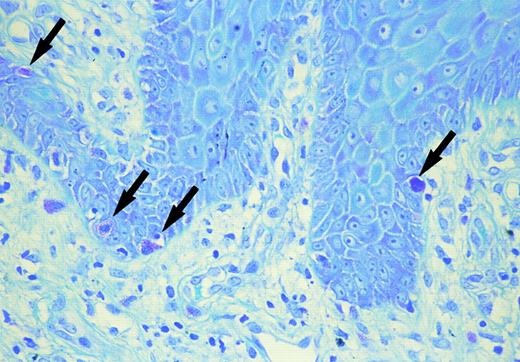

Skin biopsy specimens were fixed with 10% formalin solution and were stained with hematoxylin-eosin and toluidine blue at a pH of 2.5, 4.1, and 7.0 to identify mast cells. Mast cells containing metachromatic granules were counted under high magnification of the ×400 power-fields of a light microscope. As the mast cells were most numerous in the papillary dermis or upper dermis of the MF lesion, the number of metachromatic cells was counted in 10 fields in this layer. Immunohistochemistry was performed with a standard avidine-biotin peroxidase technique (Nichirei Co, Tokyo Japan) using recombinant anti-SCF monoclonal antibody (Genzyme, Cambridge, MA) (dilution at a final concentration of 1:50). The sections were developed with 3-amino-9-ethylcarbazole as chromogen, counterstained with hematoxylin, dehydrated, cleared, and mounted. Negative controls were prepared by omitting of the specific antibody. SCF concentration in the serum before systemic chemotherapy was determined with a sandwich enzyme-linked immunosorbent assay (ELISA) kit (Amersham, UK). As controls, serum was obtained from 3 patients with infiltrative stage MF without either diffuse pigmentation or itching, and from 10 normal volunteers (5 males and 5 females; age range, from 44 to 60 years). Increased number of mast cells were observed in the upper dermis. The number of mast cells in the upper dermis (133.2 ± 15.6/mm2 in case 1, and 113.4 ± 10.1/mm2 in case 2) was significantly higher than that of either 3 infiltrative stage MF (44.6 ± 7.8/mm2 ) (P < .005) or normal healthy skin (38.5 ± 9.1/mm2 ) (P < .005 in case 1 and P < .005 in case 2). In both cases, intra-epidermal mast cells were shown by toluidine blue staining in a specimen from thigh in case 1 and from buttock in case 2 (Fig 1). Clinically, both lesions showed marked infiltration or lichenification. Double staining of toluidine blue and Periodic acid-Schiff (PAS) staining showed mast cells to be above the basal membrane. Immunohistochemistry demonstrated positive perinuclear staining in a cytoplasmic pattern for SCF on tumor cells, mast cells, endothelial cells, and keratinocytes in the acanthotic epidermis in both cases. The serum SCF concentration was increased (1,640 pg/mL in case 1 and 1,250 pg/mL in case 2) as compared with that in the 3 patients with MF, but without any diffuse pigmentation or itching (863 ± 145 pg/mL) as well as the normal volunteers (748 ± 256 pg/mL).

Mast cells in the basal layer of the epidermis (arrow) (toluidine blue).